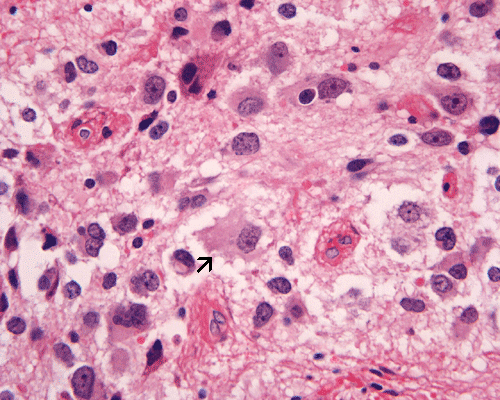

Desmoplastic infantile ganglioma: Ganglionic cells are highlighted by the arrow.